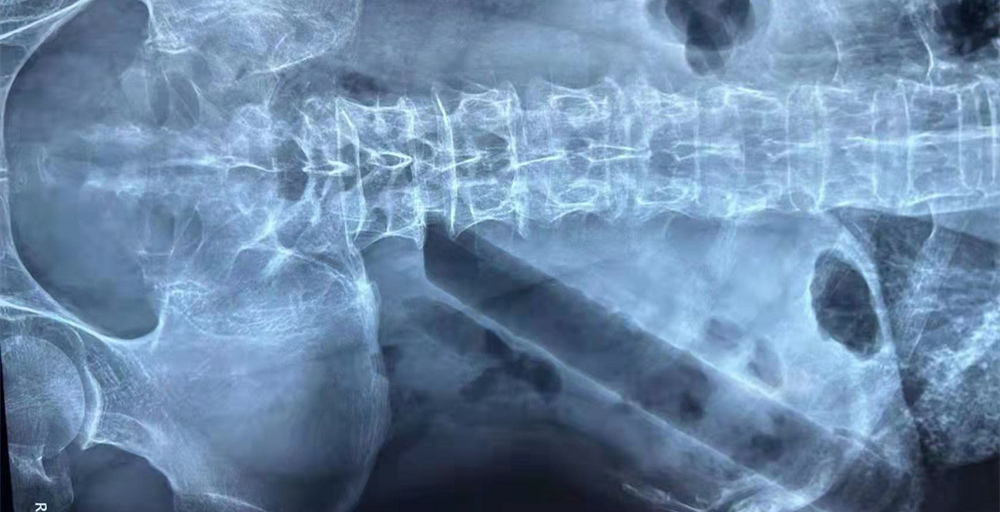

- 肛肠二科成功完成一例高难度结肠异物取出术

- 近日,我院肛肠二科成功完成一例高龄患者高难度结肠异物取出术。 3月19日下午临近下班,肛肠二科门诊赵金龙医生接诊了一名85岁高龄的特殊患者,患者在外院行腹部平片,示结肠异